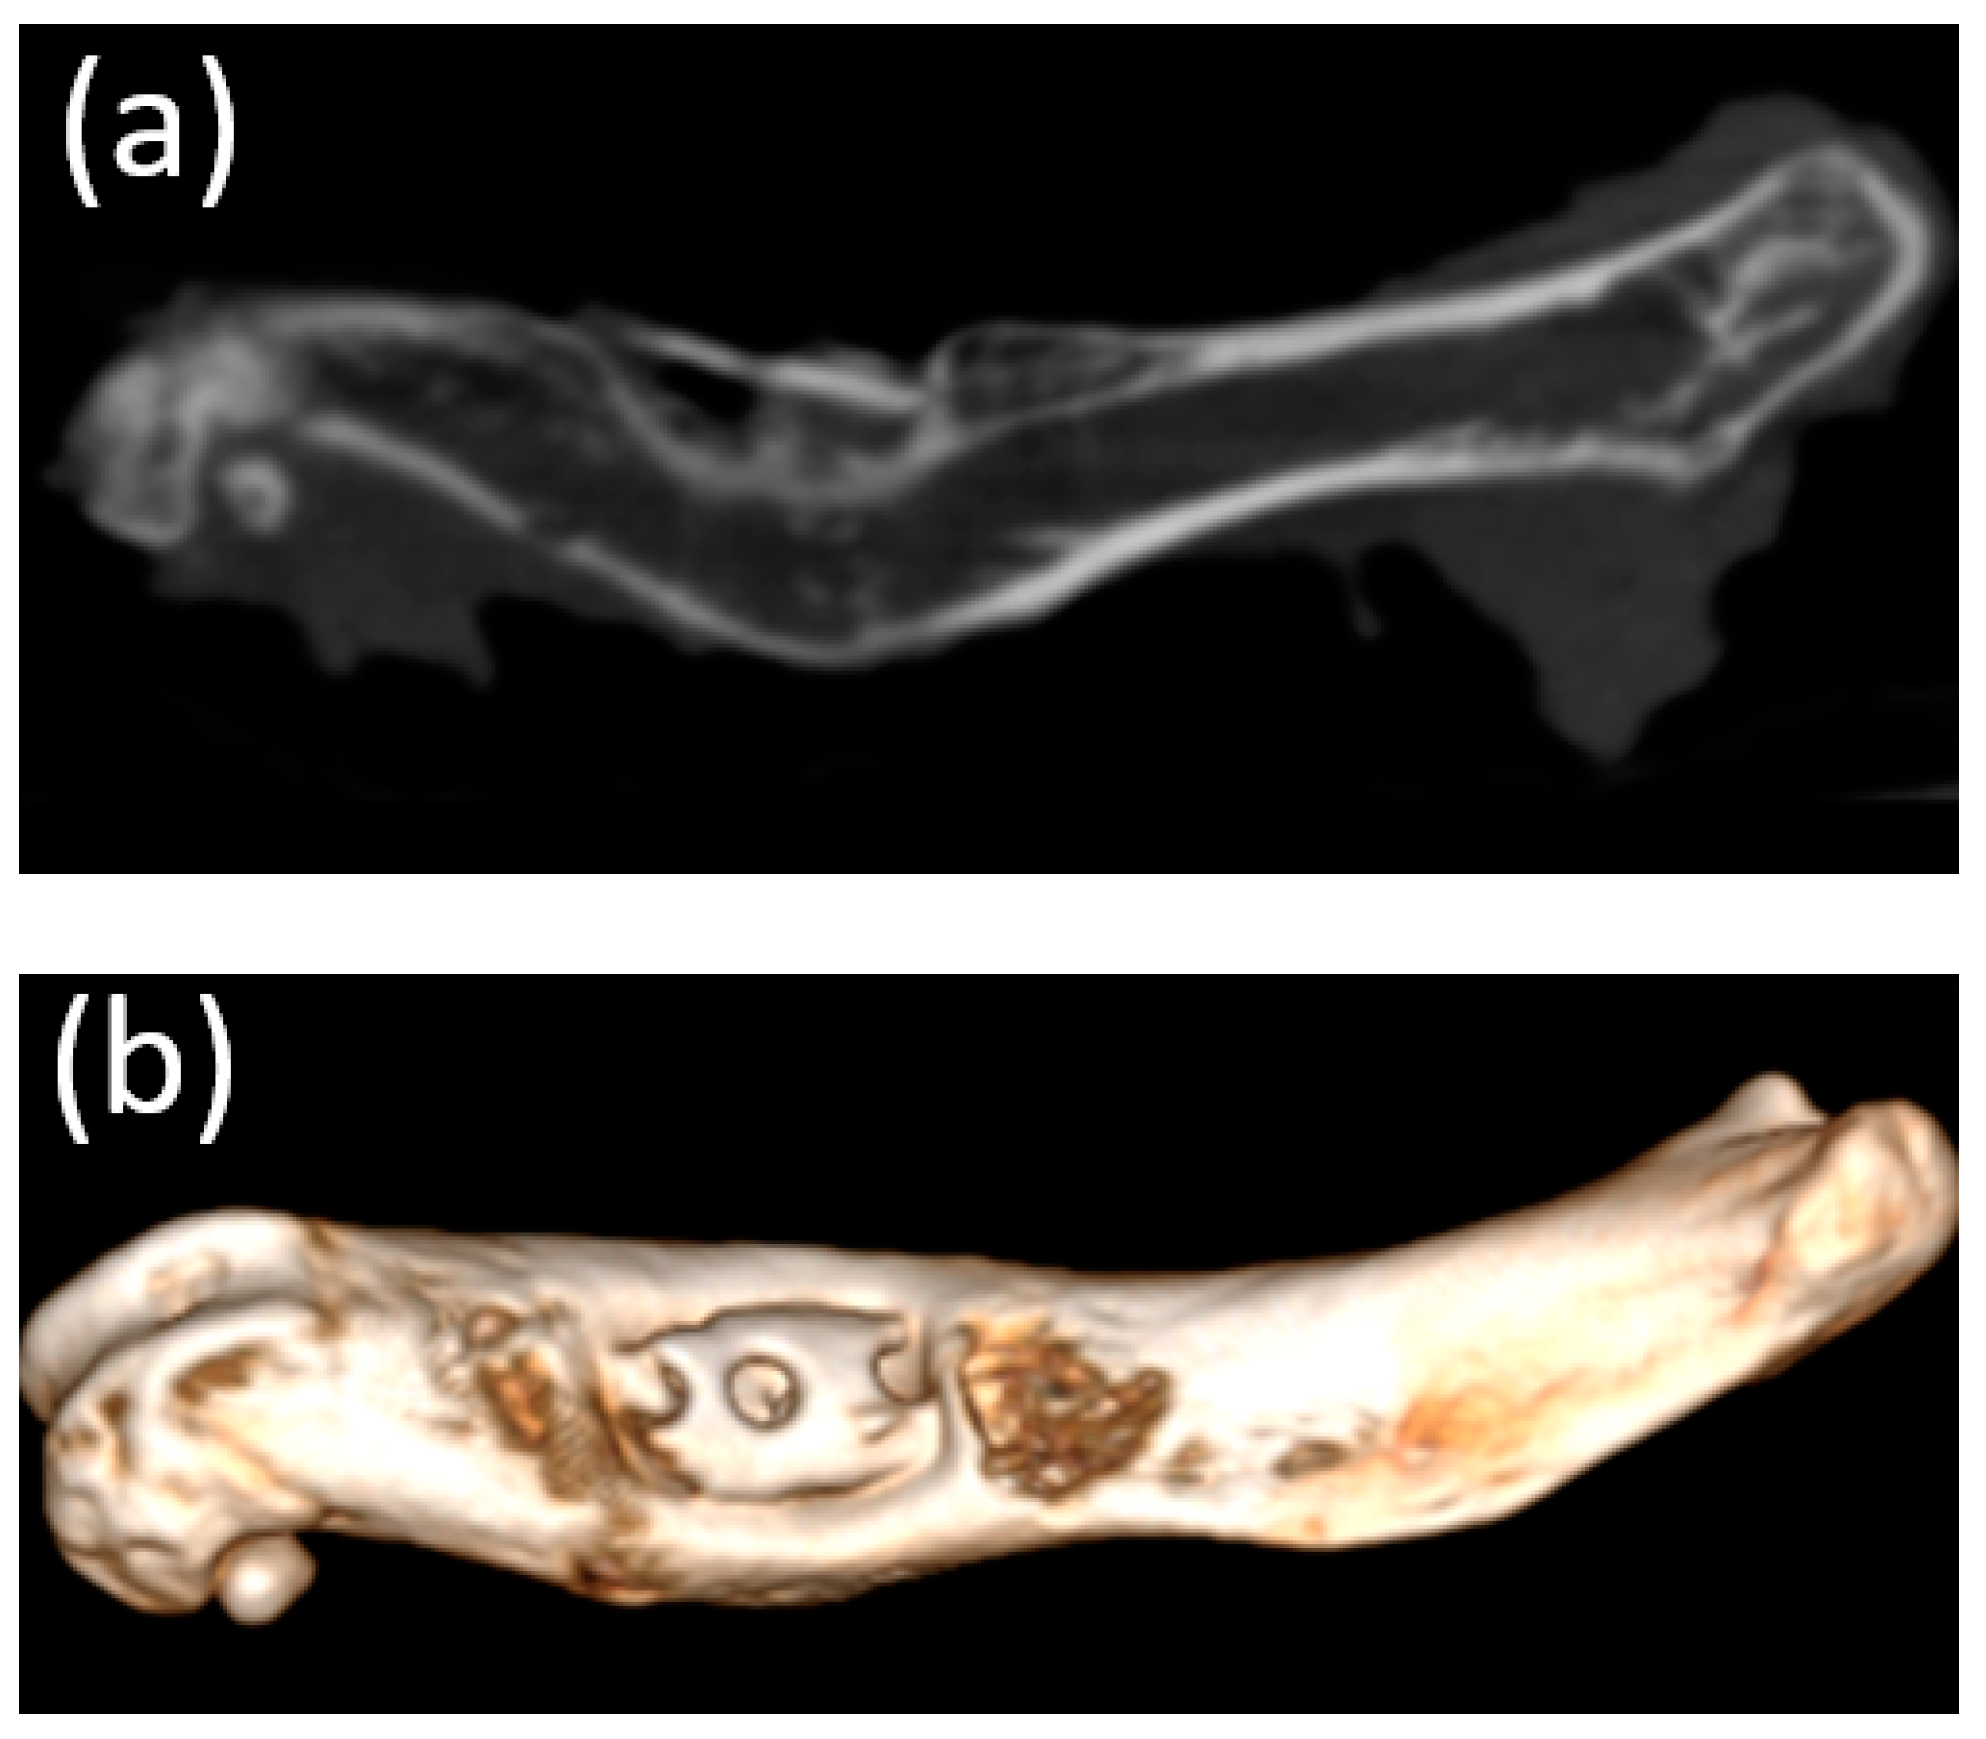

Micro-CT visualized increased density on the non-resorbed implant after 1 month (Figure 11a,b) in comparison with a slight decrease in the average density of implants after 3 months (Figure 12a,b)According to the micro-CT images 6 months after the operation, the holes formed for the implants were visualized, though the implants themselves were not visualized (Figure 13a,b). The resorption rates of the implants are shown in Table 1.

Figure 11. (a,b) Image of a fragment of the femur of an animal and the implant 1 month after implantation (obtained using micro-CT).

Figure 12. (a,b) Image of the femur of an animal 3 months after implantation (obtained using micro-CT). A decrease in the average density of the implants was visualized.